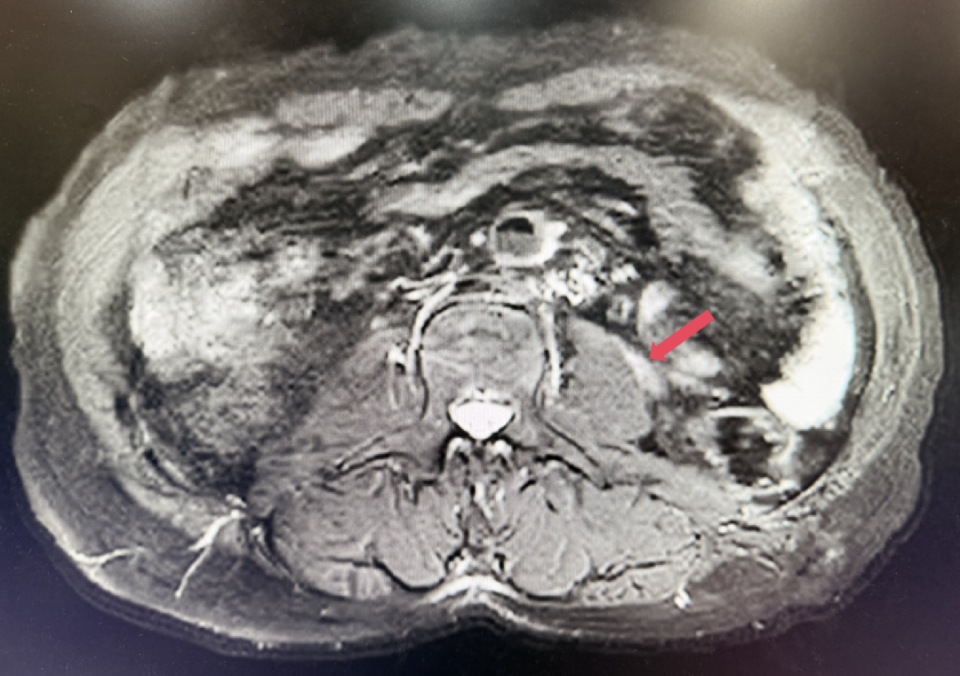

2023年3月,初始应答

2023年3月:用药6周(C2)后首次肿评,肿瘤负荷减少至76.8mm,达到PR。